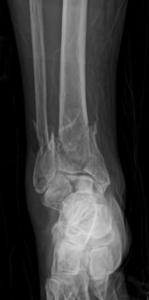

Face à ces signes, le recours à des examens complémentaires devient indispensable. Une radiographie standard de la cheville est généralement suffisante pour confirmer la présence d’un petit arrachement osseux. Dans certains cas, un scanner ou une IRM peuvent être demandés pour évaluer l’étendue des lésions ligamentaires associées ou la qualité du fragment osseux

C’est une fracture partielle où un fragment osseux se détache de la malléole externe suite à un traumatisme violent, souvent associé à une entorse.

L’arrachement osseux provoque une douleur plus intense, un gonflement important et une limitation plus sévère de la mobilité que l’entorse simple. Une radiographie permet de confirmer le diagnostic.